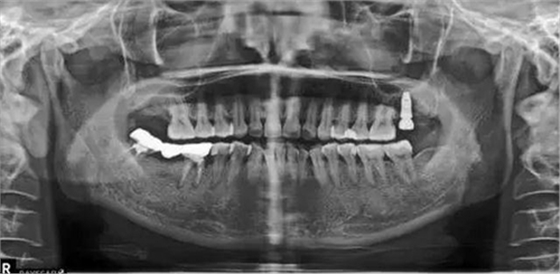

種植術后三個月復查X片??梢娮笊戏N植體已植入?;謴土己谩i_始著手進行修復進行二期手術。